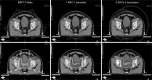

Materials and methods: Sixteen patients were studied. Prostate (PTV P ), right pelvic (PTV RtLN ) and left pelvic lymph nodes (PTV LtLN ), and organs at risk were contoured. PTV P , PTV RtLN , and PTV LtLN received 50.40 Gy followed by a boost to PTV B of 28.80 Gy. Three plans were per patient generated: IMRT, 1ARC, and 3ARC. We recorded the dose to the PTV, the mean dose (D MEAN ) to the organs at risk, and volume covered by the 50% isodose. Efficiency was evaluated by monitor units (MU) and beam on time (BOT). Conformity index (CI), Paddick gradient index, and homogeneity index (HI) were also calculated.

Results: Average Radiation Therapy Oncology Group CI was 1.17, 1.20, and 1.15 for IMRT, 1ARC, and 3ARC, respectively. The plans' HI were within 1% of each other. The D MEAN of bladder was within 2% of each other. The rectum D MEAN in IMRT plans was 10% lower dose than the arc plans (p < 0.0001). The GI of the 3ARC was superior to IMRT by 27.4% (p = 0.006). The average MU was highest in the IMRT plans (1686) versus 1ARC (575) versus 3ARC (1079). The average BOT was 6 minutes for IMRT compared to 1.3 and 2.9 for 1ARC and 3ARC IMAT (p < 0.05).